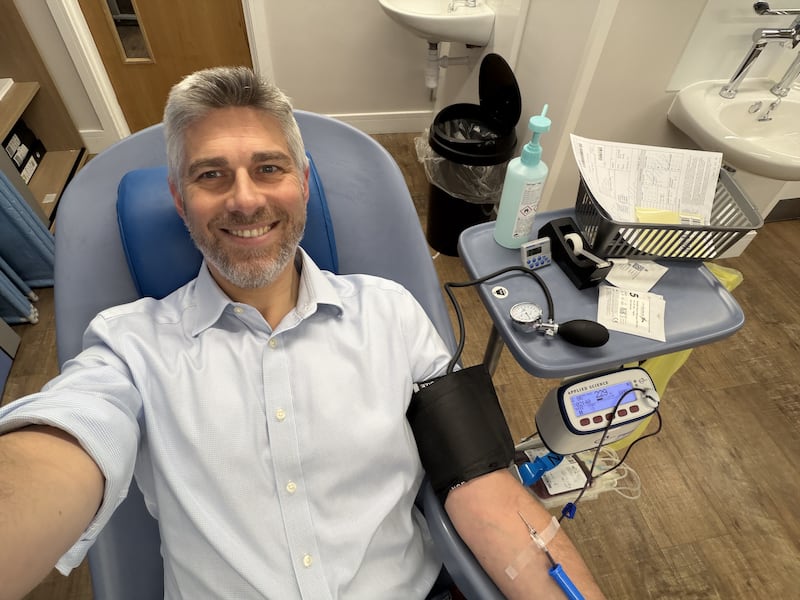

Paul Bickley, 45, who has been identified as one of the men who has donated the most for IUT procedures, said he started donating blood because of his mother’s “generous heart”.

The father of four, from Richmond, who is a vice president of an insurance company, said: “I started donating because my mum and dad donate.

“My mum told me it is a good thing to do to give back literally and metaphorically to society.

“She just has a generous heart.

Paul Bickley donating his blood (Handout/PA)

Paul Bickley donating his blood (Handout/PA)

“As the years went on and we had our own children I just realised life is very precious and that kept me donating.

“Hearing my blood was used in this way almost made me cry, to think a very small act of kindness on my part could have such a massive impact.

“It was mind-blowing and miraculous.”